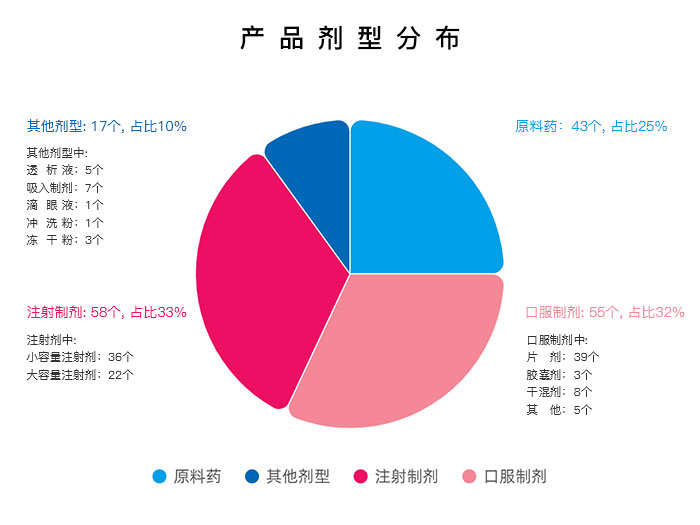

所研品种主要涉及呼吸系统、神经精神系统、消化及代谢系统、抗感染、心血管系统、基础输液 (含透析、冲洗)等治疗领域

仿制药开发剂型

★ 脂质体、微球制剂

★ 注射乳剂

★ 专线制剂

★ 冻干制剂

★ 激素类注射剂

★ 大容量注射剂

★ 常释片剂

★ 缓控释片剂

★ 复方制剂

★ 胶囊

★ 单剂量干混悬剂

★ 多剂量干混悬剂

★ 吸入制剂

★ 单剂量滴眼剂

★ 透析液

★ 冲洗液